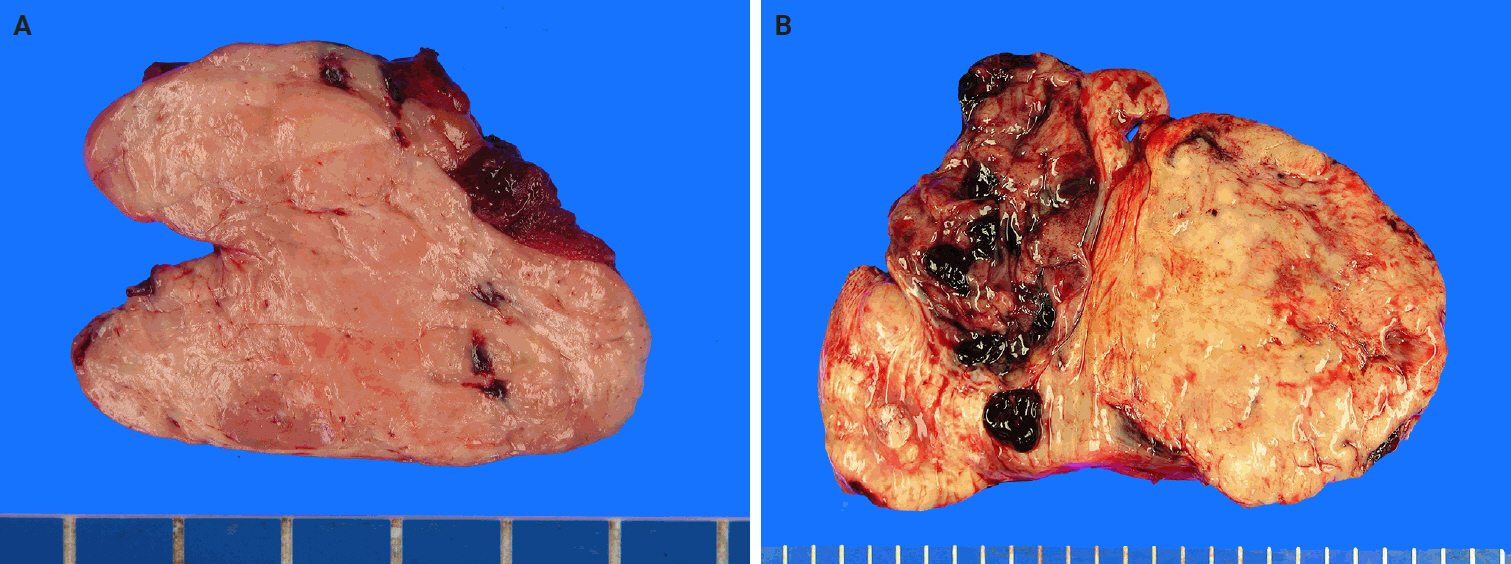

Macroscopic features

SFTs are usually well-circumscribed, solid masses ranging in size from 1 cm to greater than 25 cm, with most measuring between 5−10 cm in diameter [83,84]. The cut surface varies from firm and white in more fibrous tumors to tan and fleshy in highly cellular lesions (Fig. 2). Hemorrhage, calcification, or necrosis may occur, particularly in the larger tumors [85-88]. Benign SFTs are typically well-circumscribed, but unencapsulated, whereas malignant tumors often exhibit infiltrative borders and areas of necrosis [89].

Tumors arising from serosal surfaces often exhibit an exophytic appearance, whereas those within body cavities may be present as polypoid, stalk-attached fibrous masses [3]. Pleural SFTs are often large (>10 cm) and pedunculated, with a pedicle containing prominent feeder vessels. Some cases lack direct pleural attachment and can appear enclosed within the lung parenchyma [37].

Fig. 2.

Macroscopic findings of solitary fibrous tumor. (A) The cut surface of the tumor is well-circumscribed, with a pinkish-gray, fleshy, and solid appearance. (B) The tumor is multilobulated, with yellow-tan to gray coloration and prominent areas of hemorrhage.